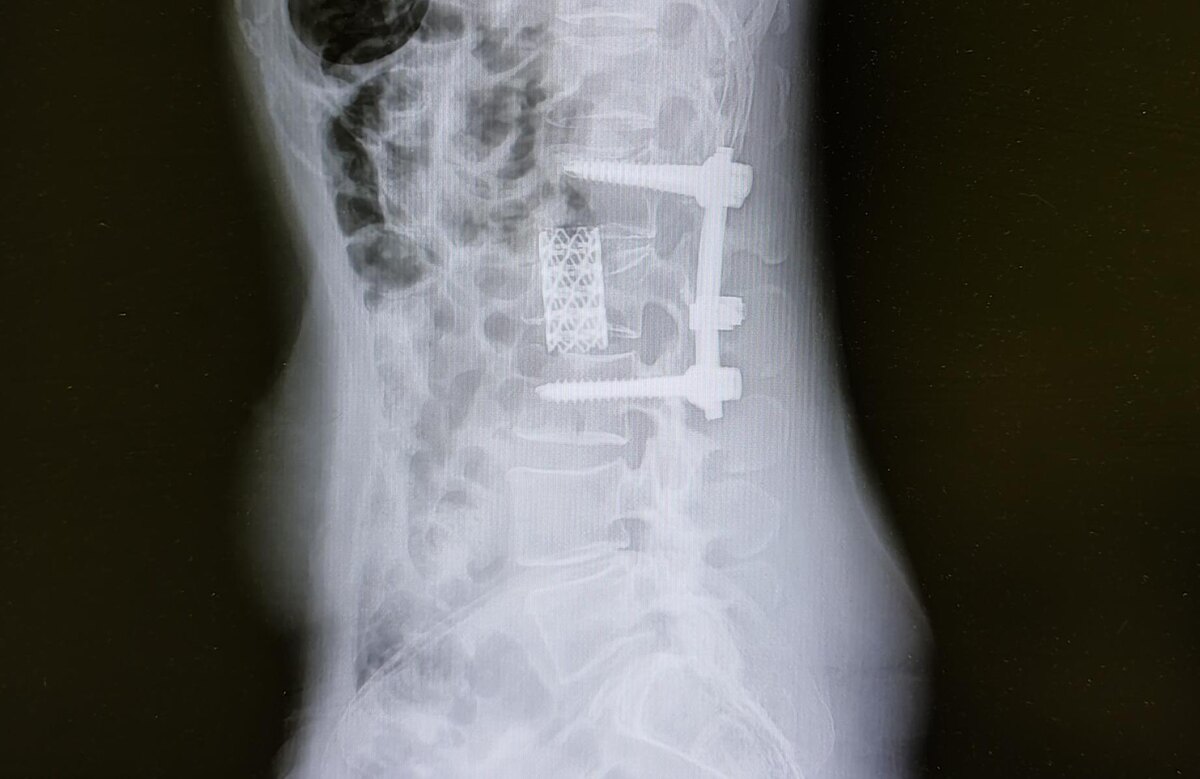

Оскольчатый перелом L2 позвонка, транспедикулярная фиксация с корпородезом MESH⁠⁠

В анамнезе оскольчатый перелом L2 позвонка, оперативное лечение.

Состояние после транспедикулярной фиксакции L1, L3 позвонков, люмботомия справа, с резекцией части тела L2 позвонка, передний корпородез MESH -по поводу травмы грудопоясничного отдела позвоночника с компрессионно-оскольчатым переломом L2 позвонка.